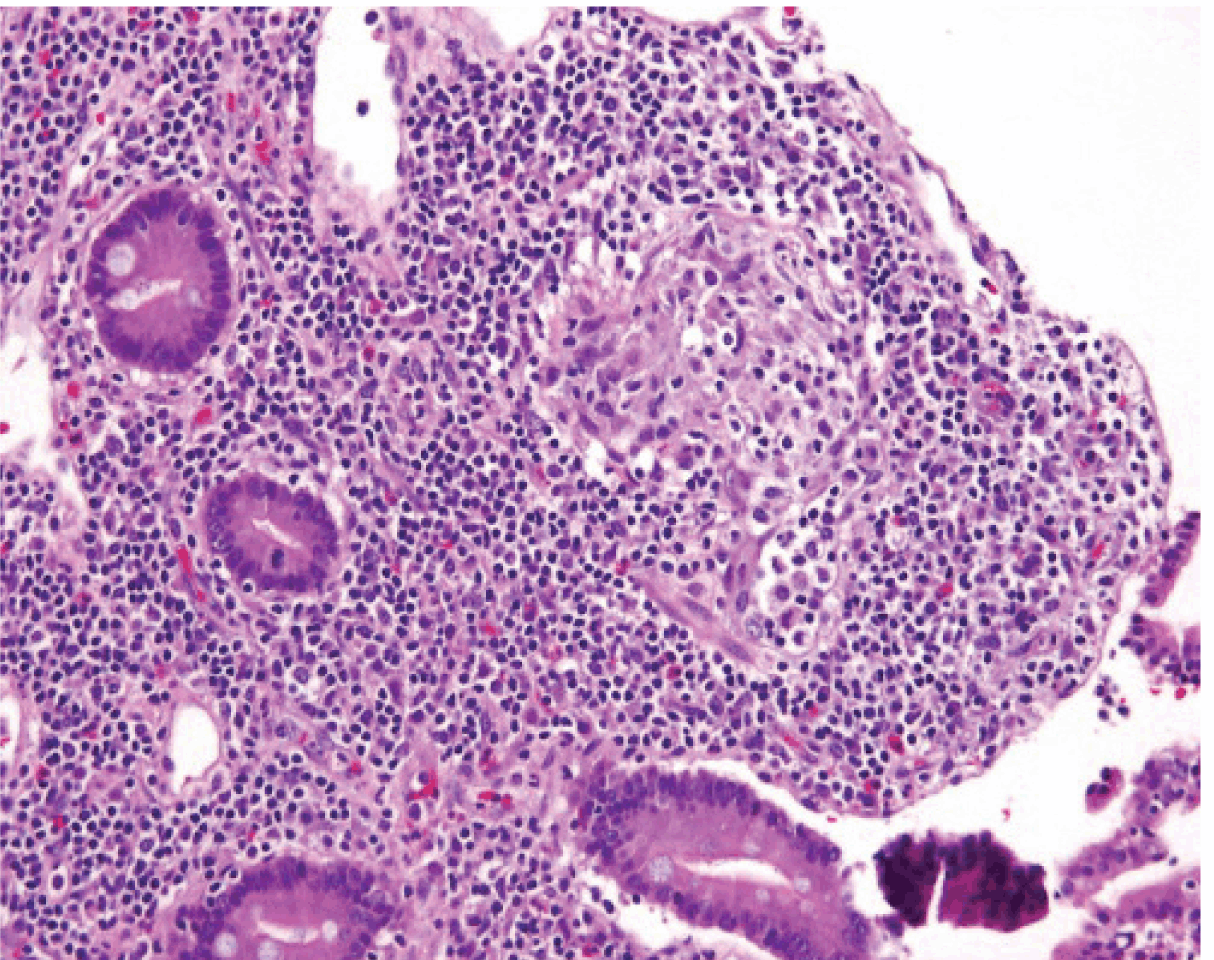

Microscopically the resected segment of the specimen demonstrated transmural inflammation with extensive pinpoint mucosal ulceration along with cobble stone linear ulcers, fistula tracts and a large area of perforation. Inflammatory pseudo-polyps were numerous. Multiple lymphoid hyperplasia with germinal centers (strings of pearls), occasional granulomas and a rare crypt abscess was noted. (Figure 5) All these findings were suggestive of Crohn’s disease.

Figure 5: Micrograph illustrating granuloma within the mucosa.